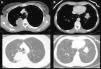

Paciente de 57 años, exfumadora, consulta por tos irritativa. La Rx de tórax identifica una masa paratraqueal derecha y un nódulo en LII con características de malignidad. La TC de tórax muestra: masa sólida, necrosada, con realce periférico en LSD (figs. 1A y C), otra lesión subpleural similar en LII (figs. 1B y D), y una adenomegalia hiliar derecha patológica. Todas las lesiones captan en el PET.

A y C) Cortes axiales de TC en ventana de mediastino y de pulmón respectivamente. Observamos una masa sólida de 6×4cm de bordes infiltrativos, con necrosis en su interior y realce periférico en segmento posterior del LSD adyacente a pleura posterior. B y D) Cortes axiales de TC en ventana de mediastino y de pulmón. Apreciamos otra lesión sólida en el LII adyacente a pleura diafragmática, de contornos infiltrativos, con menor necrosis. E y F) Cortes axiales de TC en ventana de pulmón, a los 6 meses del inicio del tratamiento con bevacizumab. En E vemos la lesión del LSD de mayor tamaño, cavitada y sin componente sólido, y en F la tumoración sólida del LII de menor tamaño y atenuación que en -B y -D).

Se realiza PAAF de ambas lesiones siendo la AP: adenocarcinoma de pulmón ALK no traslocado y EGFR no mutado. Se inicia tratamiento con taxol-carboplatino-bevacizumab (antiangiogénico) y bevacizumab de mantenimiento.

En el TC de control la lesión del LSD aumentó de tamaño, se cavitó y disminuyó el componente sólido (fig. 1E). El tumor del LII y la adenomegalia disminuyeron de tamaño y atenuación (fig. 1F).

En los últimos años ha habido cambios trascendentales en el tratamiento del cáncer de pulmón avanzado con la introducción de dianas moleculares, terapia inmunológica y antiangiogénica, con mecanismos de acción y patrones de respuesta distintos a la quimioterapia convencional. Los efectos de los antiangiogénicos incluyen no solo el cambio de tamaño sino la aparición de cavitación (20%), considerada criterio de buena respuesta al tratamiento. Aunque aumente el tamaño global de la lesión, la cavitación y disminución del componente sólido, se considera respuesta positiva1.